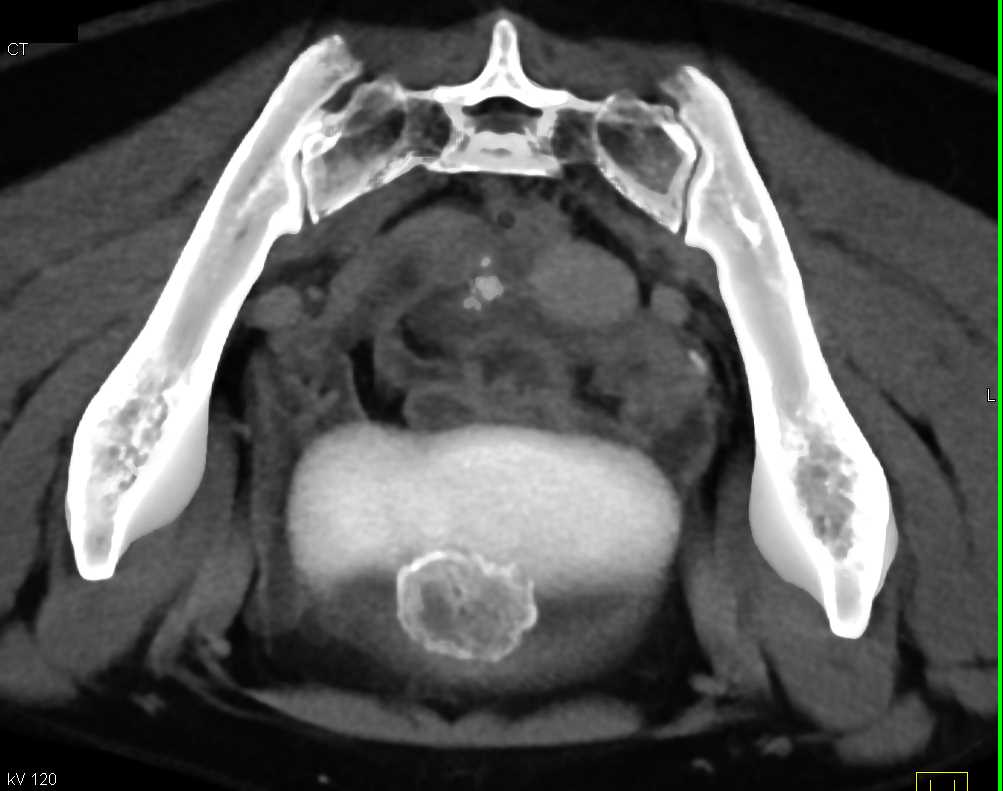

Urachal Carcinoma of the Bladder